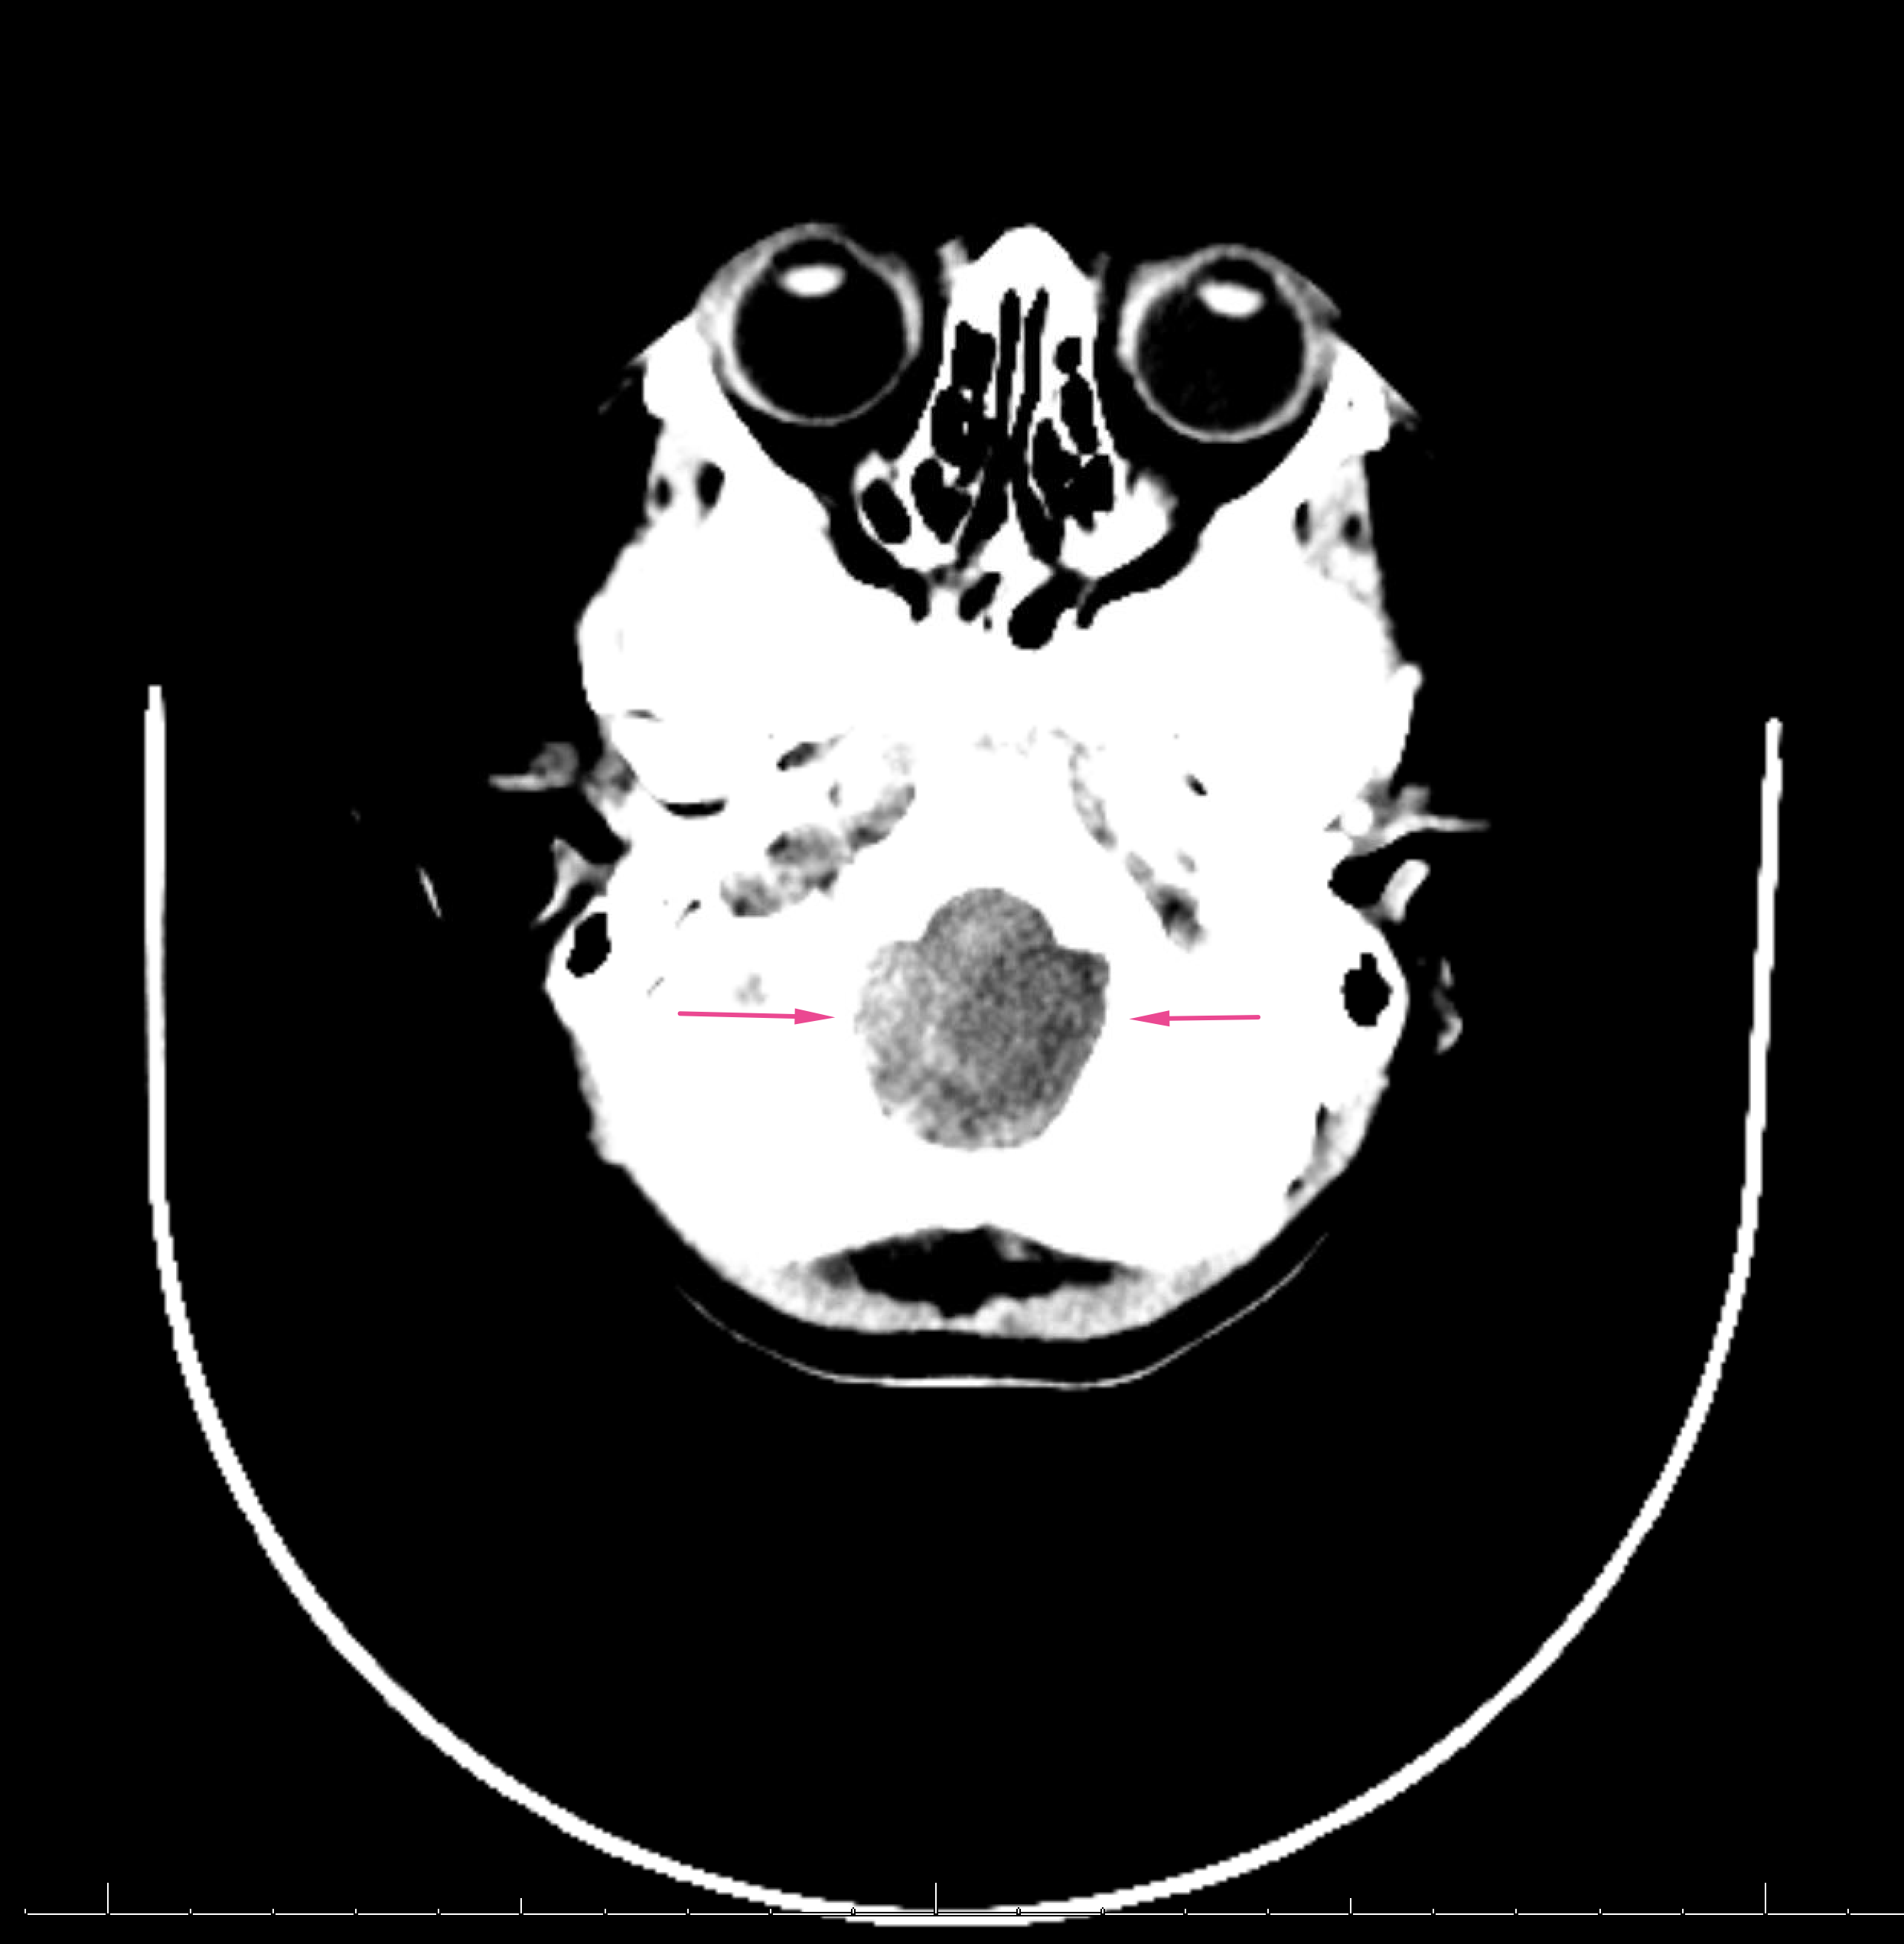

Age: 2

Sex: Male

Indication: Trauma, evaluate for brain death

Radiotracer: Tc99m ECD

Sample ReportBrain perfusion is present in the bilateral cerebral cortex and cerebellum. These findings are not consistent with brain death.